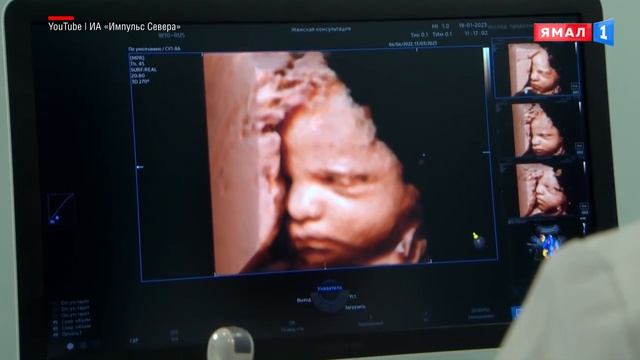

В пяти городах ЯНАО можно пройти УЗИ на премиум-оборудовании